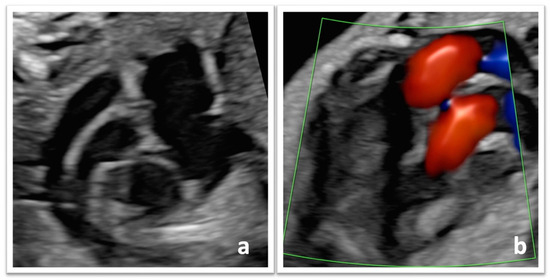

- Bravo-Valenzuela, N.J.; Peixoto, A.B.; Júnior, E.A. Prenatal diagnosis of transposition of the great arteries: An updated review. Ultrasonography 2020, 39, 331–339. [Google Scholar] [CrossRef]